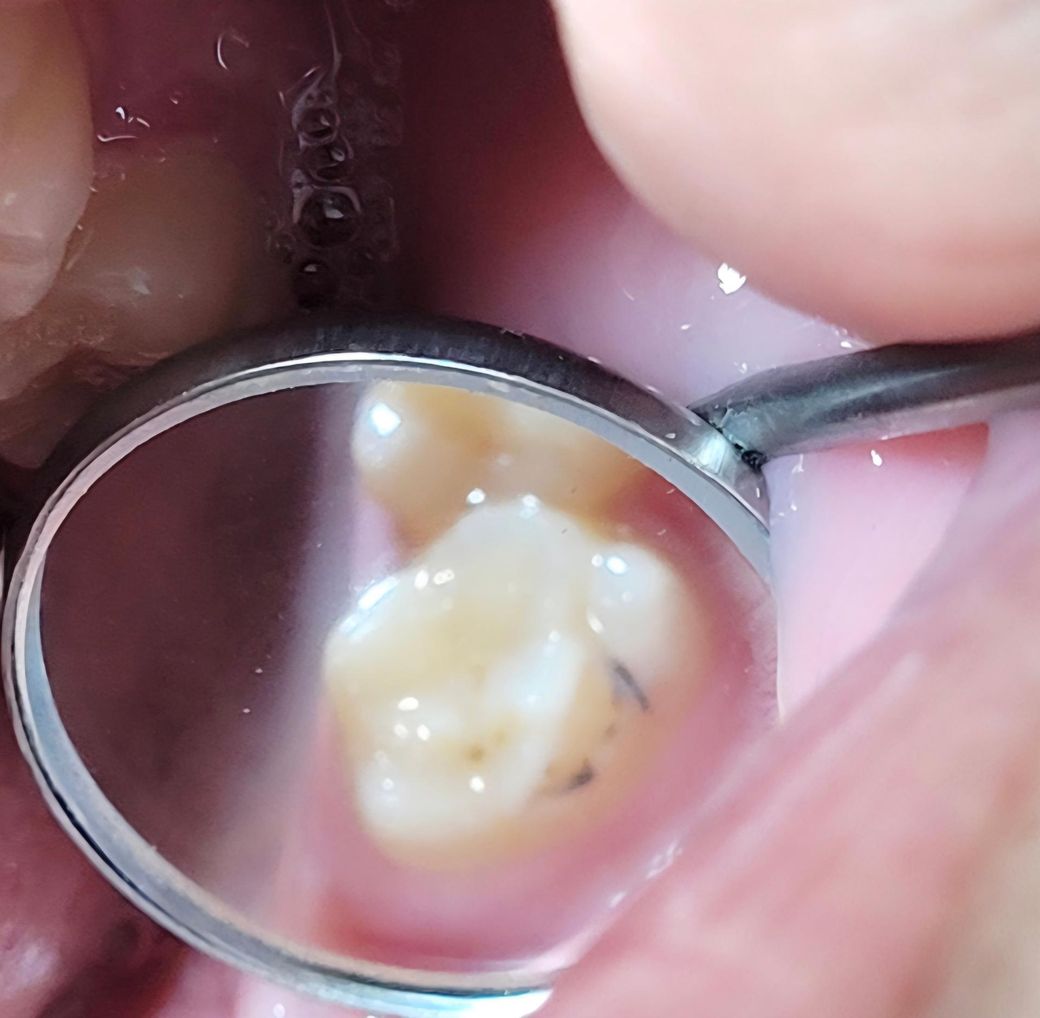

1번사진 24년 9월

• 1번 째 사진